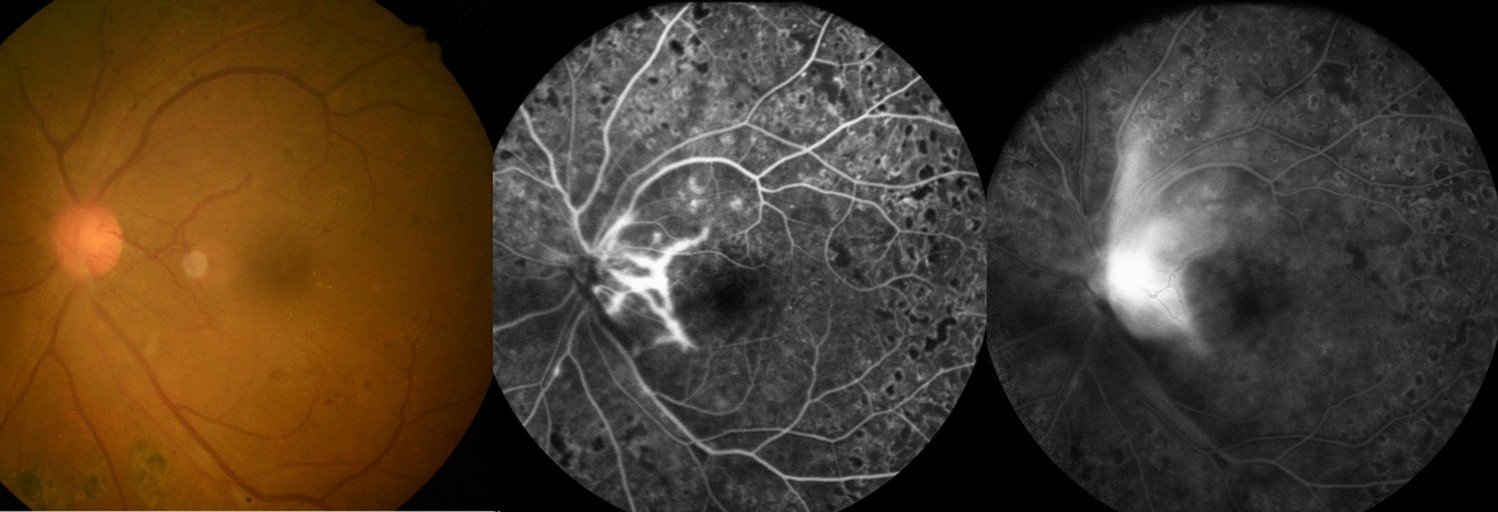

Fundus photographs and fluorescein angiography of case 1 at 6 months after PRP. Engorged new vessel on disc and severe leakage therefrom are observed.